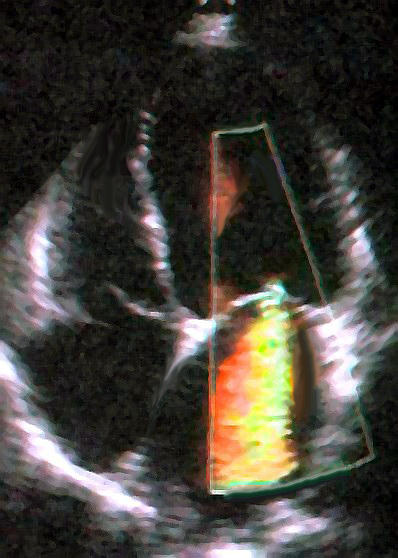

심장 초음파 검사는 승모판 역류(MR)의 진단을 확인하는 데 일반적으로 사용된다.[16] 경흉부 심장 초음파(TTE)에서 컬러 도플러 혈류 검사는 심실 수축기 동안 좌심실에서 좌심방으로 혈액의 제트가 흐르는 것을 보여준다. 또한 확장된 좌심방과 심실, 그리고 감소된 좌심실 기능을 감지할 수 있다.[11] 필요한 경우, 심장의 뒤쪽도 볼 수 있으므로 경식도 심장 초음파 검사(TEE)로 더 선명한 영상을 얻을 수 있다.[17]

승모판 역류(MR)의 정도를 정량화하는 또 다른 방법은 판막 수준에서 역류 흐름의 면적을 결정하는 것이다. 이것을 역류 개구부 면적이라고 하며, 이는 승모판의 결함 크기와 상관관계가 있다. 개구부 면적을 측정하는 데 사용되는 특정 심장 초음파 검사 기법 중 하나는 근위 등속 표면 면적 (PISA, Proximal Isovelocity Surface Area) 측정이다. PISA를 사용하여 승모판 역류 개구부 면적을 결정하는 단점은 심장 주기의 한 시점에서 흐름을 측정하므로 역류 제트의 평균 성능을 반영하지 못할 수 있다는 것이다.